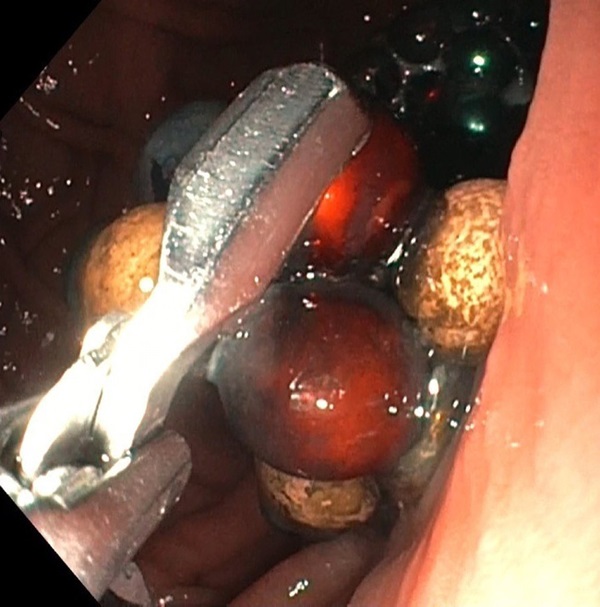

Chỉ mới 2 tháng trước, hồi tháng 2, dịch vụ báo chí của sở y tế Moscow đưa tin, các bác sĩ phẫu thuật tại Bệnh viện Nhi đồng 9 mang tên Speransky ở Moscow đã lấy ra 117 quả bóng từ tính trong dạ dày của một đứa trẻ 1 tuổi.

Cậu bé chơi cùng chị gái, đến khi mẹ bọn trẻ dọn dẹp đồ chơi, phát hiện thiếu bóng từ tính và lập tức đưa cả 2 con đến bệnh viện kiểm tra. Bé gái lớn hơn không có vấn đề gì nhưng bác sĩ phát hiện nhiều bóng từ tính trong bụng bé trai 1 tuổi. Cậu bé được khẩn trương đưa vào phòng mổ.